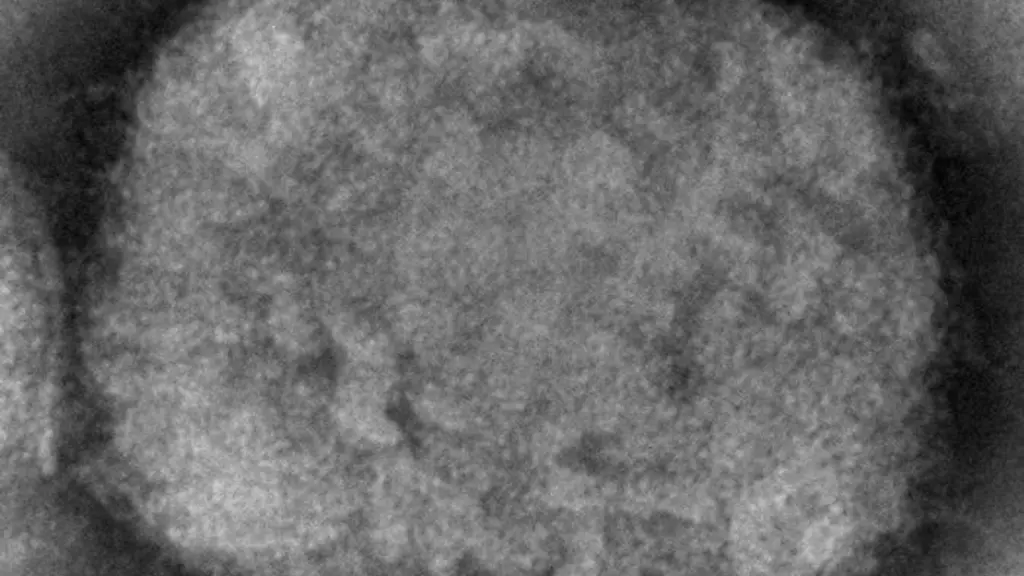

Der aktuelle Ausbruch der Affenpocken zeigt bisher Ungewohntes: Erstmals stecken sich auch Menschen außerhalb Afrikas mit dem Virus an. Über die Gefahren der Anpassung tierischer Erreger an den Menschen spricht ntv.de mit dem Virologen und Zoonose-Experten Thomas Mettenleiter.

Der aktuelle Ausbruch der Affenpocken zeigt bisher Ungewohntes: Erstmals stecken sich auch Menschen außerhalb Afrikas mit dem Virus an. Hat der Erreger sich womöglich verändert und besser an den Menschen angepasst? Schließlich sind Affenpocken seit den späten 1950er Jahren bekannt, doch bisher blieben sie in Afrika. Wird sich das nun ändern? Über die Gefahren einer scheiternden Eindämmung des Virus und den gefährlichen Trend zu tierischen Erregern spricht ntv.de mit dem Virologen und Zoonose-Experten Thomas Mettenleiter.